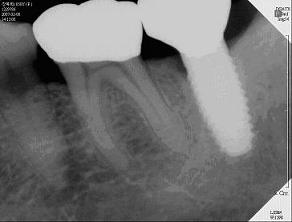

자연치아를 위한 치료법으로 대표적인 것이 바로 근관치료(신경치료)다. 근관치료는 염증이 일어난 신경조직을 잘라낸 후 그 공간을 적절한 재료로 충전시키는 방법이다. 치료는 2~3일 간격으로 3~4회 정도 진행되며, 인체의 신경을 직접 접촉하는 만큼 통증을 수반하기도 하지만 대부분 마취제 사용으로 큰 고통없이 치료가 가능하다.

10%의 가능성이 현실이 돼 근관치료가 실패했을 경우 미세치근단수술이나 재이식수술을 하면 80% 이상 살릴 수 있다. 이 교수는 "이렇게되면 자연치아보존을 통한 치료성공률이 98%에 육박하게돼 오히려 임플란트와 같은 인공보철물의 치료성공률보다 더 높다"고 말했다.

미세치근단수술은 치아의 염증이 근관치료로 해결되지 않고 깊어져 뿌리 밑 턱뼈까지 도달했을때 염증을 제거하기 위해 하는 치료법이다. 미세현미경을 활용해 뿌리의 염증조직과 치아뿌리 끝 일부를 제거하는 수술로 제거된 부분에 충전물을 채워 완전히 막는 방식이다.